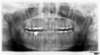

Panoramique